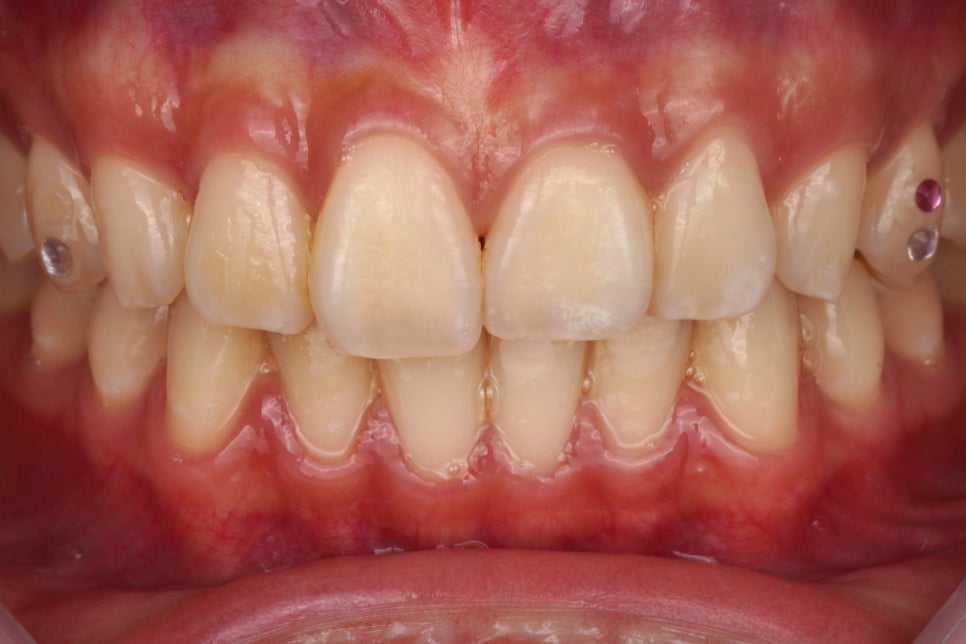

출처 아카이브 열기오늘도 투스잼 제거하러 한분이 오셨습니다.

한지 6개월 정도 되신 것 같다고

말씀을 하셨는데 볼까요?

양쪽 치아에 있다고 말씀을 하셔서

간단히 떼어드리기로 했습니다.

보이시죠?

투스젬 큐빅이 떨어져도

접착제는 남아있다는 거.

접착제까지 떨어진다는 거 그거

거짓말이라니까요?